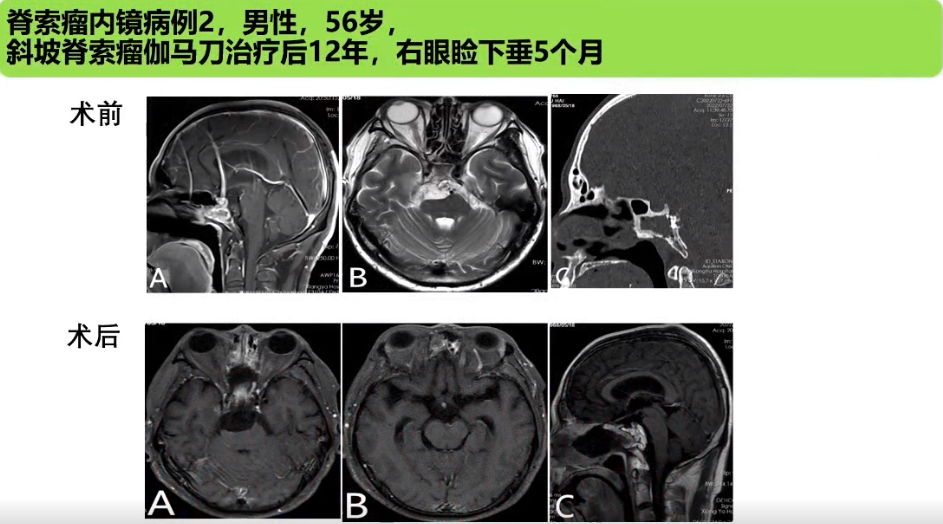

刘庆教授:经鼻内镜技术在复杂颅底肿瘤手术中的应用与思考